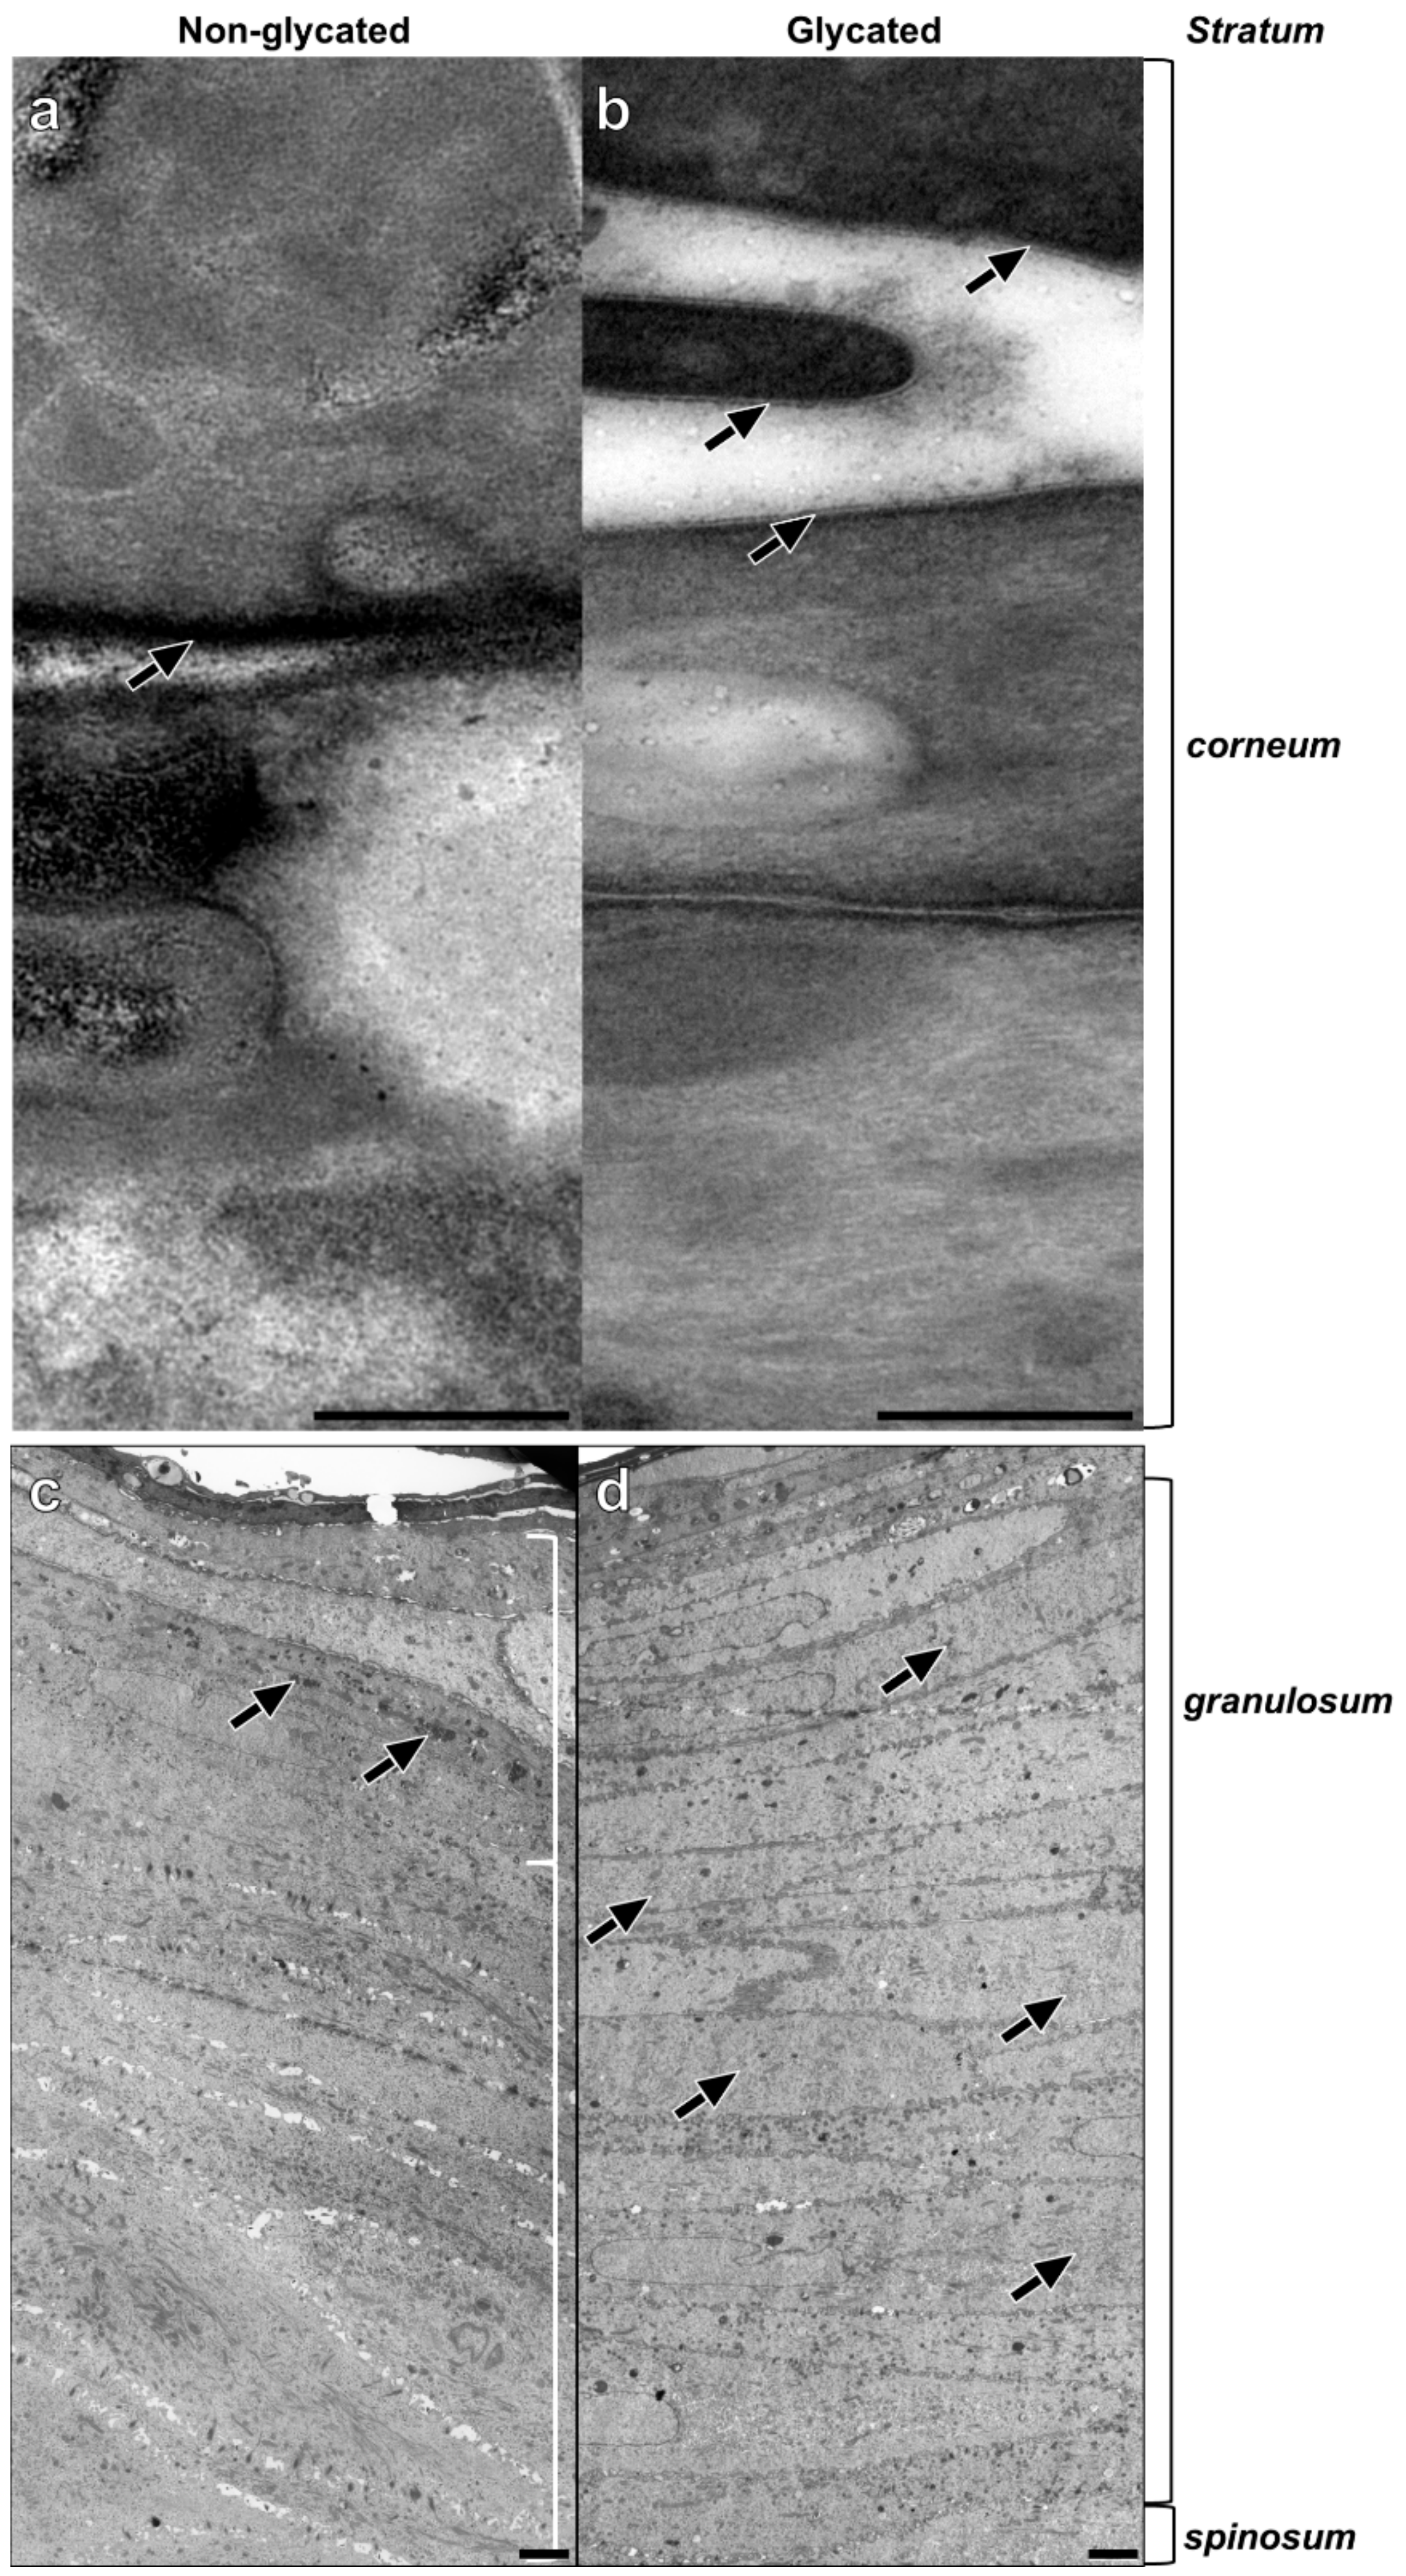

2.4. Epidermal Ultrastructure